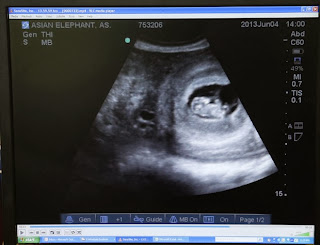

| Elefantes Africanos |